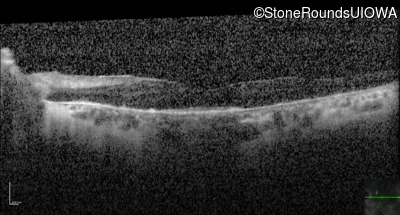

Optical Coherence Tomography - Left - 20/70 +1

Exemplar / OCT Stack